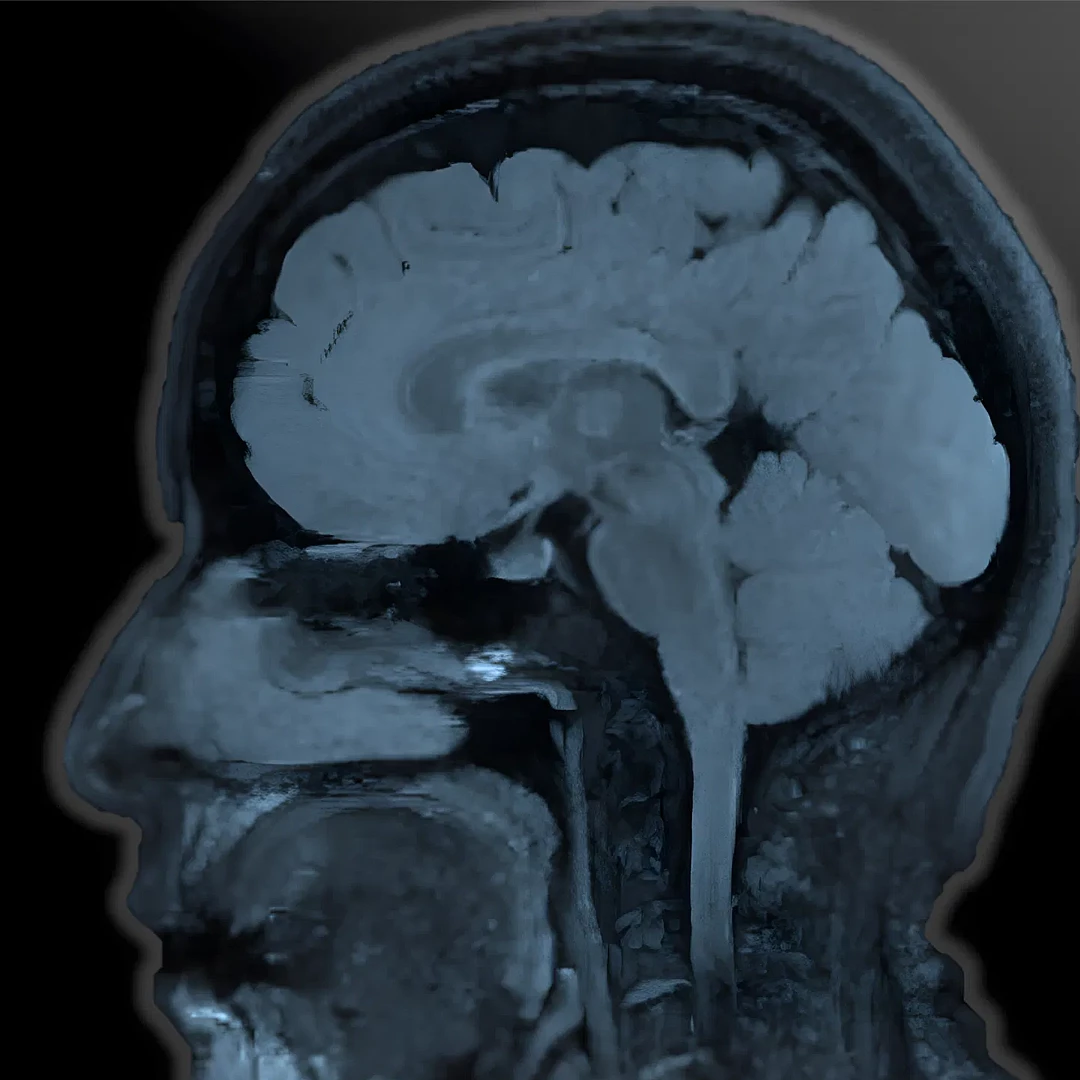

MR Neuroimaging provides high-resolution images of the brain and spinal cord using advanced MRI techniques. It aids in diagnosing neurological conditions such as tumors, strokes, and multiple sclerosis with precision.